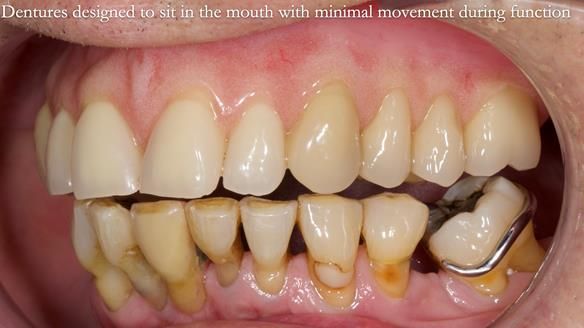

Welcome to my Newsletter 54 showing the making and fitting of dentures (a complete upper metal reinforced denture, a lower immediate partial denture and a definitive Scandinavian designed, metal based lower partial denture) for David, a 75 -year-old man. The full protocol workflow is presented including the use of dentate photographs to mimic his natural teeth.

- Current complete upper denture had many technical problems. Poor retention, support, stability and tissue fit.

- Missing teeth on the lower right side. This makes the upper denture tip when chewing and biting.

- The remaining lower 9 teeth had periodontal disease. Syed Abad, Specialist in Periodontics at the practice managed it.

Interestingly we found that the upper complete denture when finished and fitted didn’t have good enough retention for David’s satisfaction. It was relined by adding compound to the buccal flanges – to almost overextend into the sulcus to ‘create’ a sulcus, followed by using a light bodied silicone impression material. This improved the function of the C/-considerably. A lower Scandinavian hygienically designed lower RPD was also provided which helped with occlusal stability and reseating the upper denture – further improving the fit.